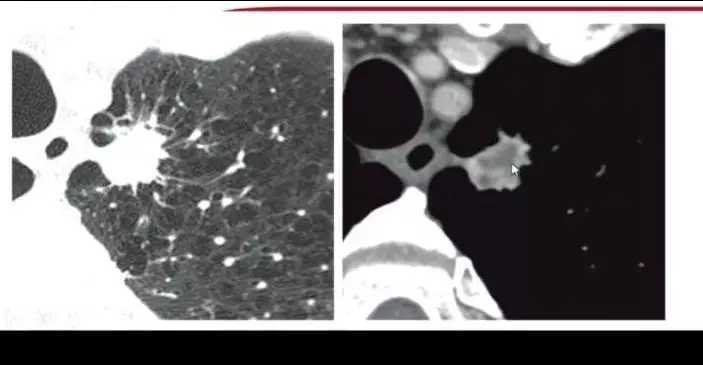

8. 机化性肺炎

机化性肺炎临床多持续存在,影像学表现为有分叶,并出现胸膜凹陷的情况。值得注意的是,机化性肺炎和真菌感染形成的肉芽肿在进行PEC-CT时摄取值同样增高,容易造成误诊。机化性肺炎通常与胸膜有牵连,胸膜出现收缩,但并非牵拉,为局限性的胸膜凹陷。

厚壁空洞,增强后厚薄不一,小叶间隔,容易误诊为肺癌。

图11 出现厚壁空洞的机化性肺炎表现

9. 球形肺不张

大量胸腔积液吸收后易出现出现球形肺不张。肺内结节有实性密度增高表现,并带有“尾巴”。

图12 球形肺不张